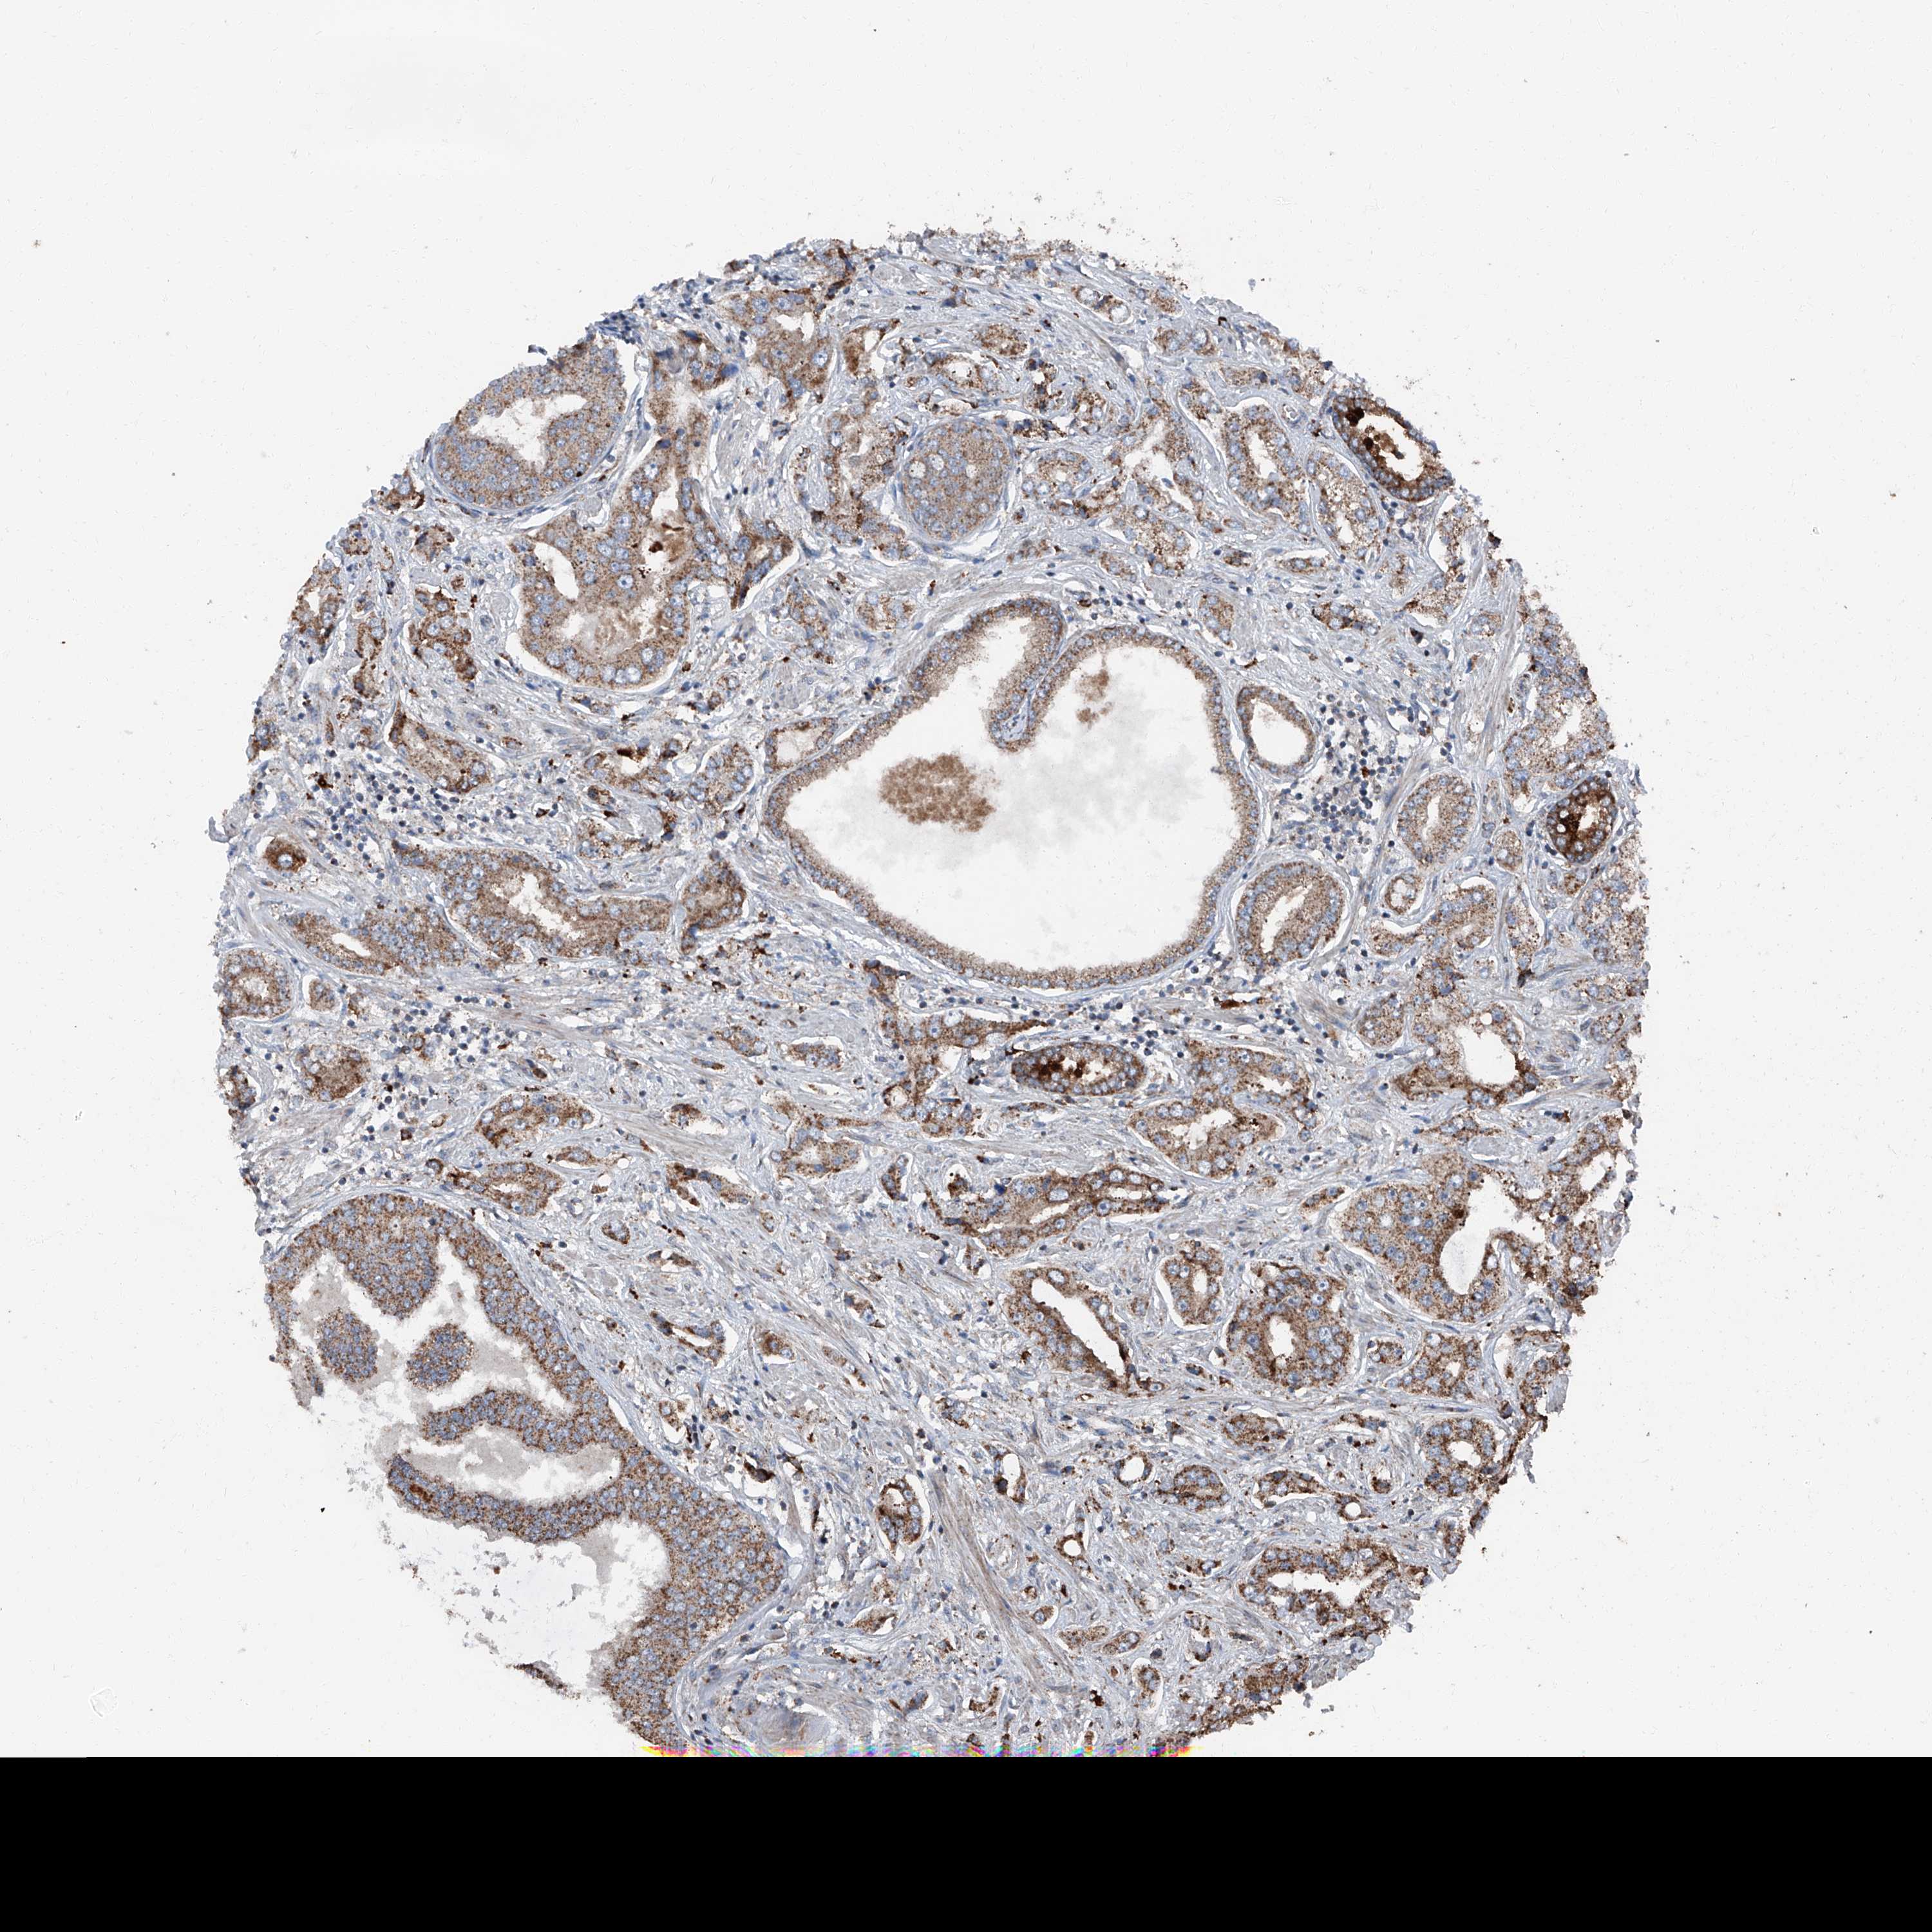

PROSTATE CANCER - Protein expressioni

A mouse-over function shows sample information and annotation data. Click on an image to view it in a full screen mode. Samples can be filtered based on level of antibody staining by selecting one or several of the following categories: high, medium, low and not detected. The assay and annotation is described here.

Antibody stainingi

Antibody staining in the annotated cell types in the current human tissue is reported as not detected, low, medium, or high, based on conventional immunohistochemistry profiling in selected tissues. This score is based on the combination of the staining intensity and fraction of stained cells.

Each image is clickable and will lead to virtual microscopy that enables deeper exploration of all samples and also displays staining intensity scores, fraction scores and subcellular localization as well as patient and tissue information for each sample.

Antibody HPA028516

Antibody HPA073571

Staining

High

Medium

Low

Not detected

Intensity

Strong

Moderate

Weak

Negative

Quantity

>75%

75%-25%

<25%

None

Location

Nuclear

Cytoplasmic/membranous

Cytoplasmic/membranous,nuclear

Adenocarcinoma, High grade

Adenocarcinoma, Low grade

Adenocarcinoma, Medium grade

Adenocarcinoma, NOS